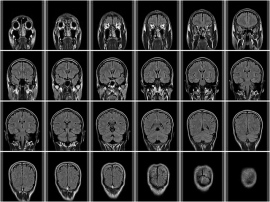

radikoがラジオ聴取と脳の成長の関係をMRI脳画像診断を用いて解明。ラジオを聴き続けることで記憶系脳が最大で2.4倍、聴覚系・理解系脳が最大で2倍成長[写真拡大]

インターネットで全国のラジオを配信しているradikoが、この俗説の科学的真偽を実証するため「脳の学校」代表の脳科学者、加藤俊徳医師の監修のもと大学生8名を対象に「ラジオを聴き続けると脳にどのような影響を与えるのか」についてMRIを用いて検証した。

聴覚情報の伝達経路は「理解系」、「聴覚系」、「言語記憶系」、「イメージ記憶系」などの領域の連携で成り立っている。この実験によって、ラジオを聴き続けることにより記憶系脳の領域が最大で2.4倍、聴覚系および理解系脳領域が最大で2倍成長し、「ラジオを聴く」という行為が脳の成長に有益な働きをもたらしていることが実証された。

ラジオを聞いている被験者のMRI画像をみると、左側頭葉にある聴覚系領域で活性エリアが最大で2倍に拡大していることが確認された。聴覚領域は左脳に存在するがMRI画像から右脳の記憶系領域の活性エリアも最大で2.4倍拡大しているのが確認できイメージ力も活性化されているようだ。

実験結果を細かに見ると、左脳の記憶系脳番地の成長が観測された被験者は8人中3人。聴覚系・理解系脳番地の成長が観測された被験者は8人中4人などとなっている。ラジオを聴き続けることは当然、左脳にある言語記憶系を刺激するであろうと予測されるが、この実験ではその予測を超えて、視覚的な想像力が換気されていることを示す右脳の記憶系脳領域を成長させることを明らかにしている。